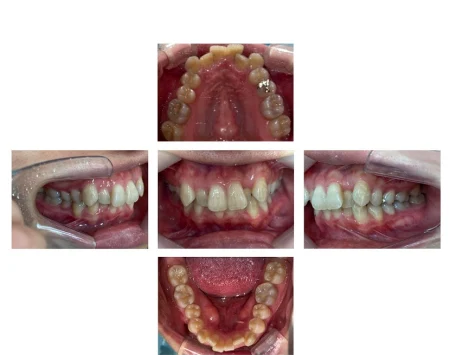

拝見したところ、上下とも歯が並ぶためのスペースが不足しており、全体的に歯が重なり合って生えている重度の「叢生(そうせい)」でした。

見た目が気になるだけでなく、虫歯や歯周病のリスクも高くなっていました。

患者様は「歯を抜かずに治療したい」とご希望でした。

取り外し式のマウスピース装置で順番に歯を動かして歯並びを整える矯正治療をご提案しました。

奥歯からしっかりと動かしてスペースを確保することで、歯を抜かずに全体の歯並びを整えられることをご説明し、同意いただきました。

マウスピースの種類は、作製できるマウスピースの枚数に制限がなく上下全体の矯正に適している「インビザラインフル」を選択しました。

矯正中は歯を動かす方向や力加減を慎重に調整し、前歯が飛び出さないよう注意しながら歯並びを改善しました。